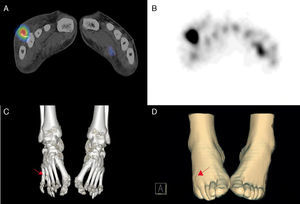

The patient was a 45-year-old man with nothing remarkable in his medical records, who presented with a 6-month history of pain and swelling in the dorsum of right foot (Fig. 1D) with purulent exudate between 4th and 5th toes. Cultures had repeatedly been negative, and he did not improve with intensive antibiotic therapy. The radiological images were not conclusive, and he came to our department to undergo scintigraphy1 with 99mTc-hexamethylpropyleneamine oxime (HMPAO)-labeled leukocytes (Fig. 1A and B). There was an increased uptake of the tracer in the fourth metatarsal 3h after injection of the radiotracer.2 The study was completed with the acquisition of a single photon emission computed tomography/computed tomography and 3D reconstruction (3D SPECT/CT) which made it possible to locate the infectious process in soft tissue of the dorsum of the foot. It was related to a foreign body in the distal third of the fourth metatarsal (Fig. 1C), unknown until then. After its surgical removal, the patient's improvement was excellent in a few weeks.

Single photon emission computed tomography/computed tomography (SPECT/CT) after the intravenous administration of autologous leukocytes labeled with 20mCi of 99mTc-hexamethylpropyleneamine oxime (HMPAO). Hybrid SPECT/CT image (A) and SPECT image (B) showing the increased uptake in the fourth metatarsal of right foot. 3D reconstruction with bone window (C) that enables the correlation of the scintigraphic findings with the presence of a foreign body (arrow), that can be discerned by the impression it leaves on the surface of the skin (D).